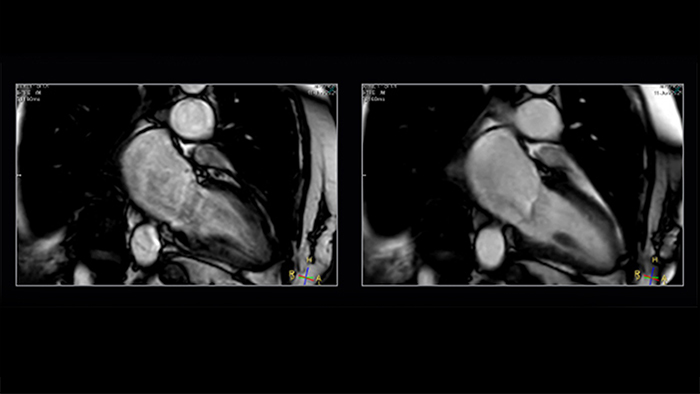

Shorter-breath holds are particularly impactful for patients who cannot manage the length of the breath-hold instruction. Mr. Strachan commented, “using Compressed SENSE sometimes pulls a non-diagnostic study into being a diagnostic study. That itself is very valuable.” For example, see Fig. 1

Figure 1. Shortening acquisition and denoising from C-SENSE provides confidence in long-axis cine of a patient with atrial fibrillation. Left to right: SENSE x2, C-SENSE x4

The impact of motion is reduced by Compressed SENSE in two ways. As well as allowing data to be acquired in a shorter duration [2] (so less movement [2] has occurred during readout), it also intrinsically includes denoising, which is a feature of any compressed sensing based acceleration method. If a motion artefact has a similar appearance to the smeared-aliasing which is deliberately produced by the incoherent undersampling which Compressed SENSE employs, the reconstruction may filter some of it out.